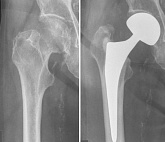

Еndoprosthesis of hip joint

In the late stages of arthrosis of the hip joint, medial fractures of the femoral neck in the older age group, the only way to recover is to replace the affected joint with an artificial joint - arthroplasty.

This method allows you to return the limb's limb, the full volume of movements in the affected joint, to save from constant pain and crunch during movements and, as a consequence, to return the patient to a full active life.

Below are presented X-ray photographs and photographs, illustrating the amount of motion in the affected joint before and after surgery.